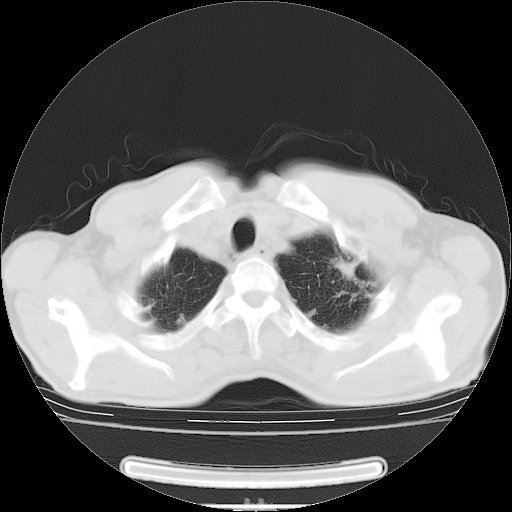

男性患者,63岁。右侧胸背部疼痛2月,加重一周。

考虑:右肺中央型肺癌并右肺下叶不张;两肺尖继发性肺结核。

右肺下叶支气管狭窄闭塞,右下肺不张,气管前间隙淋巴结肿大,两上肺散在分部粟粒灶,沿肺血管支气管束分部,血管支气管束走形较为光滑。考虑右肺中心型肺癌合并肺不张,纵隔淋巴结转移,两上肺癌性淋巴管炎

右肺下叶中心性肺癌并纵隔淋巴结转移,左侧肋骨转移。双肺上叶继发性结核表现。

1)右肺下叶中心性肺癌并纵隔淋巴结转移,两肺转移,左侧肋骨转移。2)双肺上叶继发性结核。

右肺下叶中心性肺癌并纵隔淋巴结及两肺、左侧肋骨转移。双肺上叶继发性结核表现。